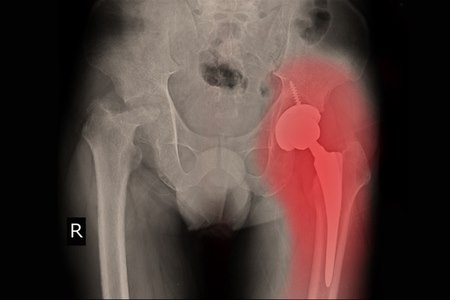

המטופלים שעברו ניתוח בגישה הקדמית הם שבעי הרצון ביותר. צילום: שאטרסטוק

יש לציין כי כל עוד הניתוח עבר בהצלחה וללא סיבוכים, הרי שלטווח הארוך אין הבדל מבחינת שביעות הרצון של המטופלים, בין הניתוחים השונים: כולם מספקים תוצאות איכותיות ומסוגלים להחזיר את התפקוד ולהעלים את הכאבים. יחד עם זאת, כפי שציינו, בחודש וחצי לאחר הניתוח, המטופלים שעברו ניתוח בגישה הקדמית הם שבעי הרצון ביותר, משום שתקופת השיקום קלה יותר באופן משמעותי, בהשוואה לשתי הגישות האחרות.